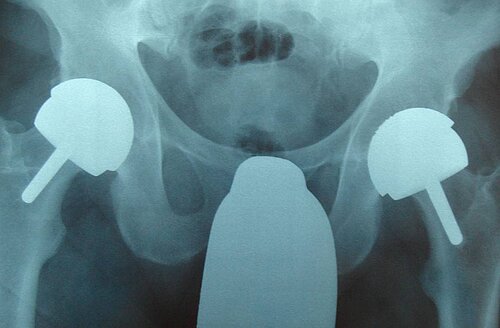

Der Wissenschaftliche Ausschuss „SCENIHR – Scientific Committee on Emerging and Newly Identified Health Risks“ der Europäischen Kommission hat 2014 seine finale Fachmeinung zur Sicherheit von Metall-auf-Metall-Gelenkprothesen mit besonderem Fokus auf Hüftimplantate veröffentlicht. Hierbei werden unter anderem die „Konsensus-Empfehlungen zur Handhabung von Metall-auf-Metall Gleitpaarungen“ befürwortet, welche auf Expertenmeinungen eines internationalen multidisziplinären Gremiums basieren.